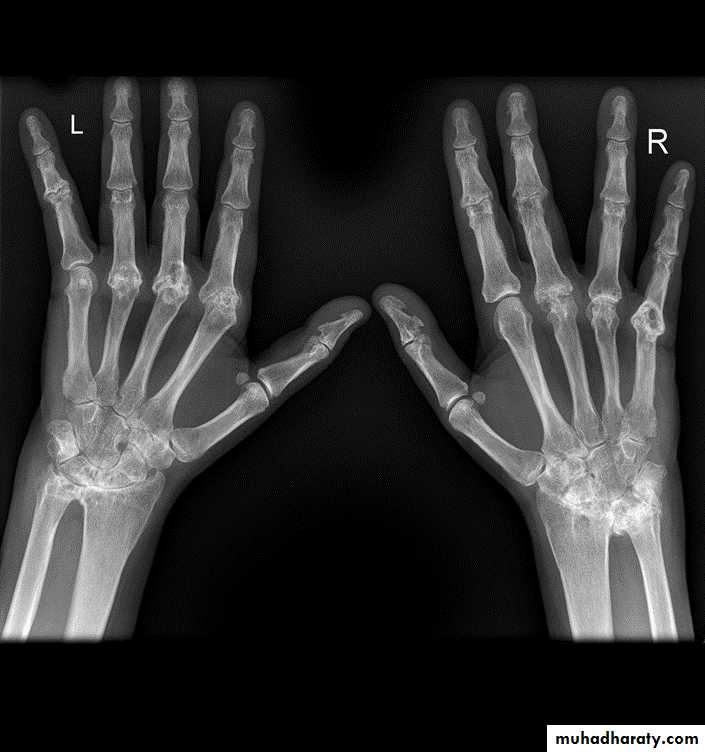

Gross rheumatoid arthritis at the carpus with ulnar deviation,

subluxation and joint narrowing at the metacarpophalangeal joints.Boutonniere deformities are present at the index and little fingers.